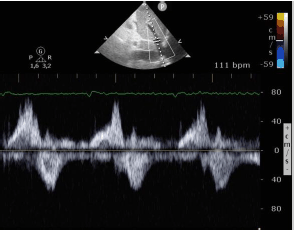

Considere um paciente de 72 anos, portador de fibrilação atrial e doença pulmonar crônica, admitido com dispneia e edema de membros inferiores.

Com base na imagem do fluxo da veia supra-hepática a seguir, assinale a alternativa que apresenta a hipótese diagnóstica mais provável.